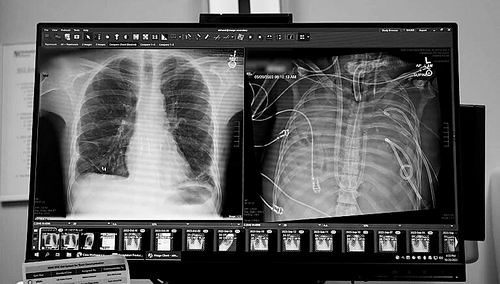

X光片显示的一名33岁患者的新肺(左)和旧肺。图片来源:美国西北大学

本报讯一名33岁的男子在没有肺的情况下存活了48小时。一个医疗团队用一套体外人工肺系统维持了这名男子的生命,直到他接受了双肺移植手术。1月30日,相关研究结果发表于《医学》。